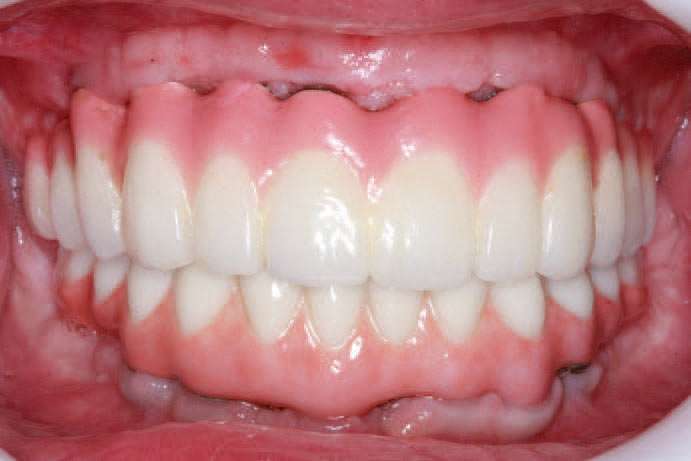

The retracted view and the patient’s full-face smile are demonstrative of the excellent laboratory communication and careful attention to each step in this patient’s journey (Figures 20 and 21). His oral care required extra attention due to his emotional and psychological deficits caused by his hydrocephaly. While dentists cannot guarantee the longevity of prostheses, the journey from this patient’s beginning to his new oral restorative beginning creates hope and changes interpersonal feelings and responsibility. The implant placement and number should allow for optimal mastication throughout his life with proper maintenance and homecare (Figure 22).